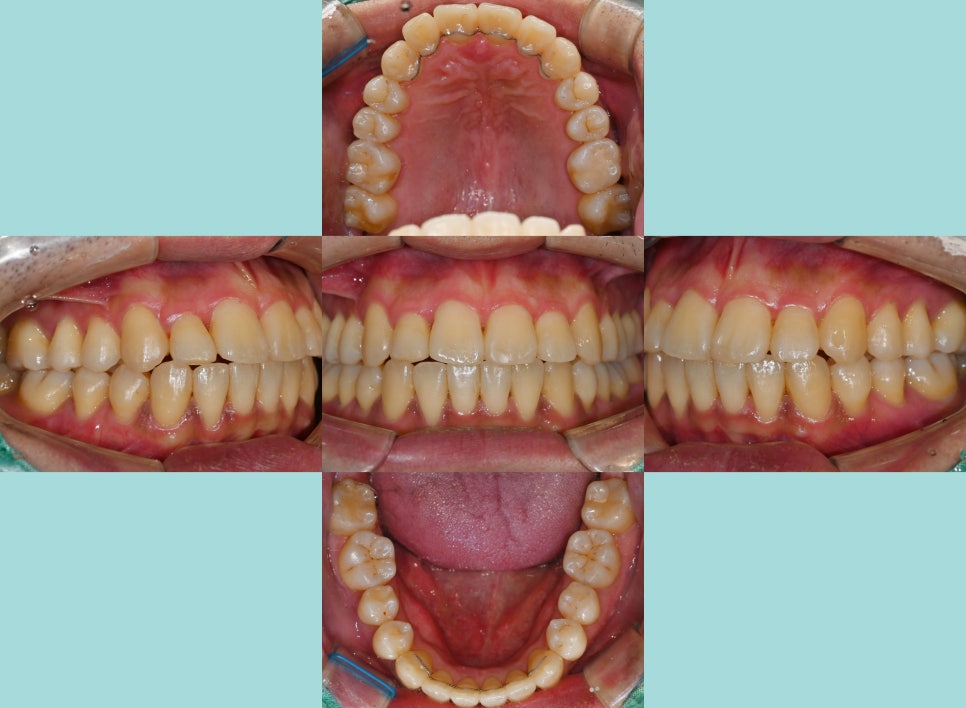

최종 완료된 모습에서는

전과 달리 가지런해진 배열로

많이 깔끔해진 느낌이 드는데요.

반대로 물리고 있었던 12번도

이제는 전방으로 이동이 잘 되어

현재는 윗니가 아랫니를 피개하는 형태로

잘 유지를 하고 있습니다.

앞니 뻐드렁니로 돌출되어 나왔던 부분도

후방 견인 과정을 통해

자연스러운 아치를 가질 수 있도록

마무리하면 모든 과정은 끝납니다.

전반적인 총생 치료로 인해

구강 내 많은 좋은 변화들이 일어나

인상 또한 밝고 깔끔해진 느낌을 받습니다.

치료 기간: 22.12~24.09